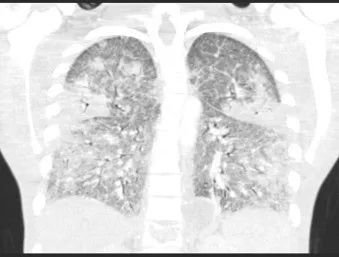

全血白细胞计数为13.4*109/L,血红蛋白8.5g/dL,血小板138/μL,C-反应蛋白28.8(正常值<3.0)。动脉血气分析显示pH值为7.30,PCO2为48.2,PO2为71.8,血培养呈阴性,进行BAL培养(包括细菌培养、病毒培养、真菌培养)。胸部X线及胸部CT显示弥漫性斑片状阴影(图1.2)。颈椎、胸椎和腰椎的CT扫描显示椎体病变(图3.4)。由于脾脏有多处病变,也进行了脾活检(图5)。

图2 胸部CT扫描:双肺均出现梯状浑浊及磨玻璃影,弥漫性间隔增厚,可见散在结节,右上叶最明显